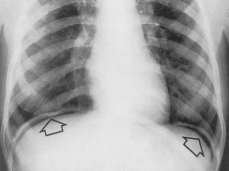

PNEUMOPERITONEUL prezenta aerului liber în cavitatea peritoneala.

Se evidentiaza pe radiografiile în pozitie verticala ca o zona transparenta semilunara, localizata sub una sau ambele cupole diafragmatice. Cantitatea de aer poate fi foarte mica aparând ca o linie discreta, curbliniara subdiafragmatica, sau foarte mare atingând o înaltime de 4-5 cm.

În radiografiile efectuate în decubit lateral stîng, imaginea trebuie cautata între fata laterala a ficatului si peretele costal, iar în cele efectuate în decubit dorsal cu raza orizontala si film lateral - periombilical sau între ansele intestinale care apar bine conturate de aerul dintre ele.